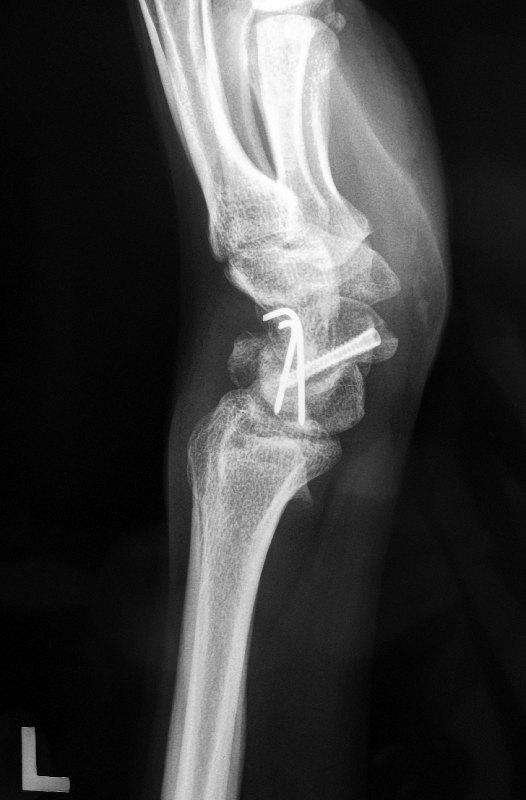

The fracture went on to heal over the next 2 to 3 months. This is how it looked like after the scaphoid fracture had healed.

The 2 wires along the luno-triquetral joint were surgically removed at 3 months after the surgery.

The patient underwent hand occupational therapy and achieved a very good result.